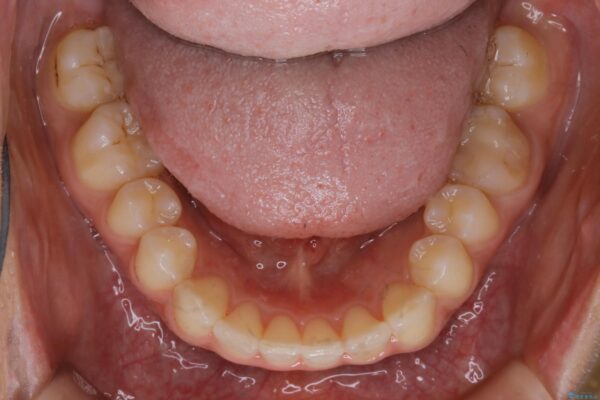

気になるガタツキと噛み合わせを改善したいとご来院されました。

下の歯列よりも上の歯列が前に出ている状態を治すため、マウスピース矯正に加え、患者様にゴムかけのご協力をいただきました。その結果、ガタつきが改善し、上下の噛み合わせが適切な位置で合うようになりました。

歯並びが悪くなる原因の一つに「歯列弓の狭窄」というものがあります。

奥歯や前歯が内側(舌側)に倒れ込んでしまったり、歯が生えてくる位置が内側になってしまうことにより歯並びのアーチが狭くなってしまうことを言います。

このような場合、歯並びのアーチを拡大してあげるだけでもガタつきを無くすためのスペースがかなり作れることがあります。